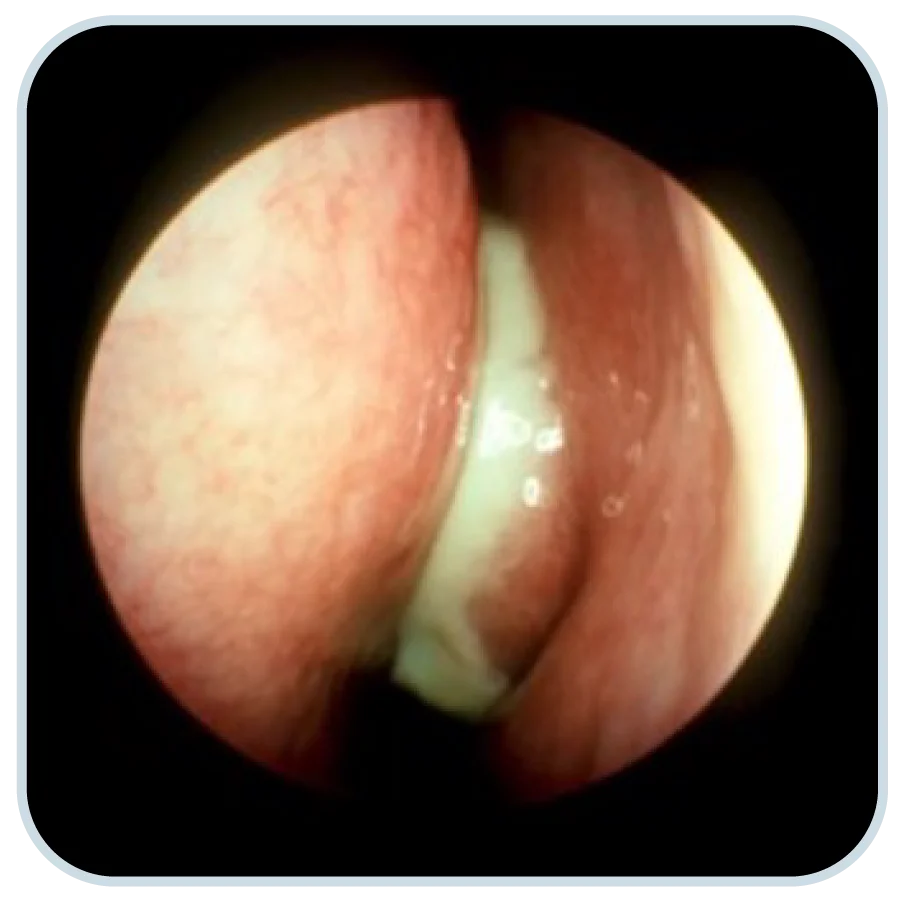

鼻咽喉內視鏡檢查